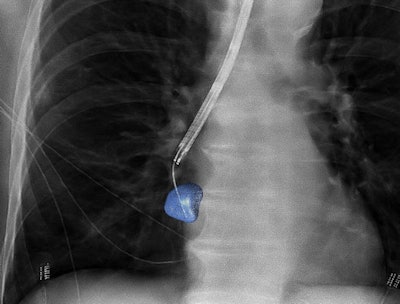

3D image guidance provided via conebeam CT and "augmented" fluoroscopy can improve accuracy in biopsies of peripheral lung lesions. CBCT Image courtesy of Philips Healthcare.